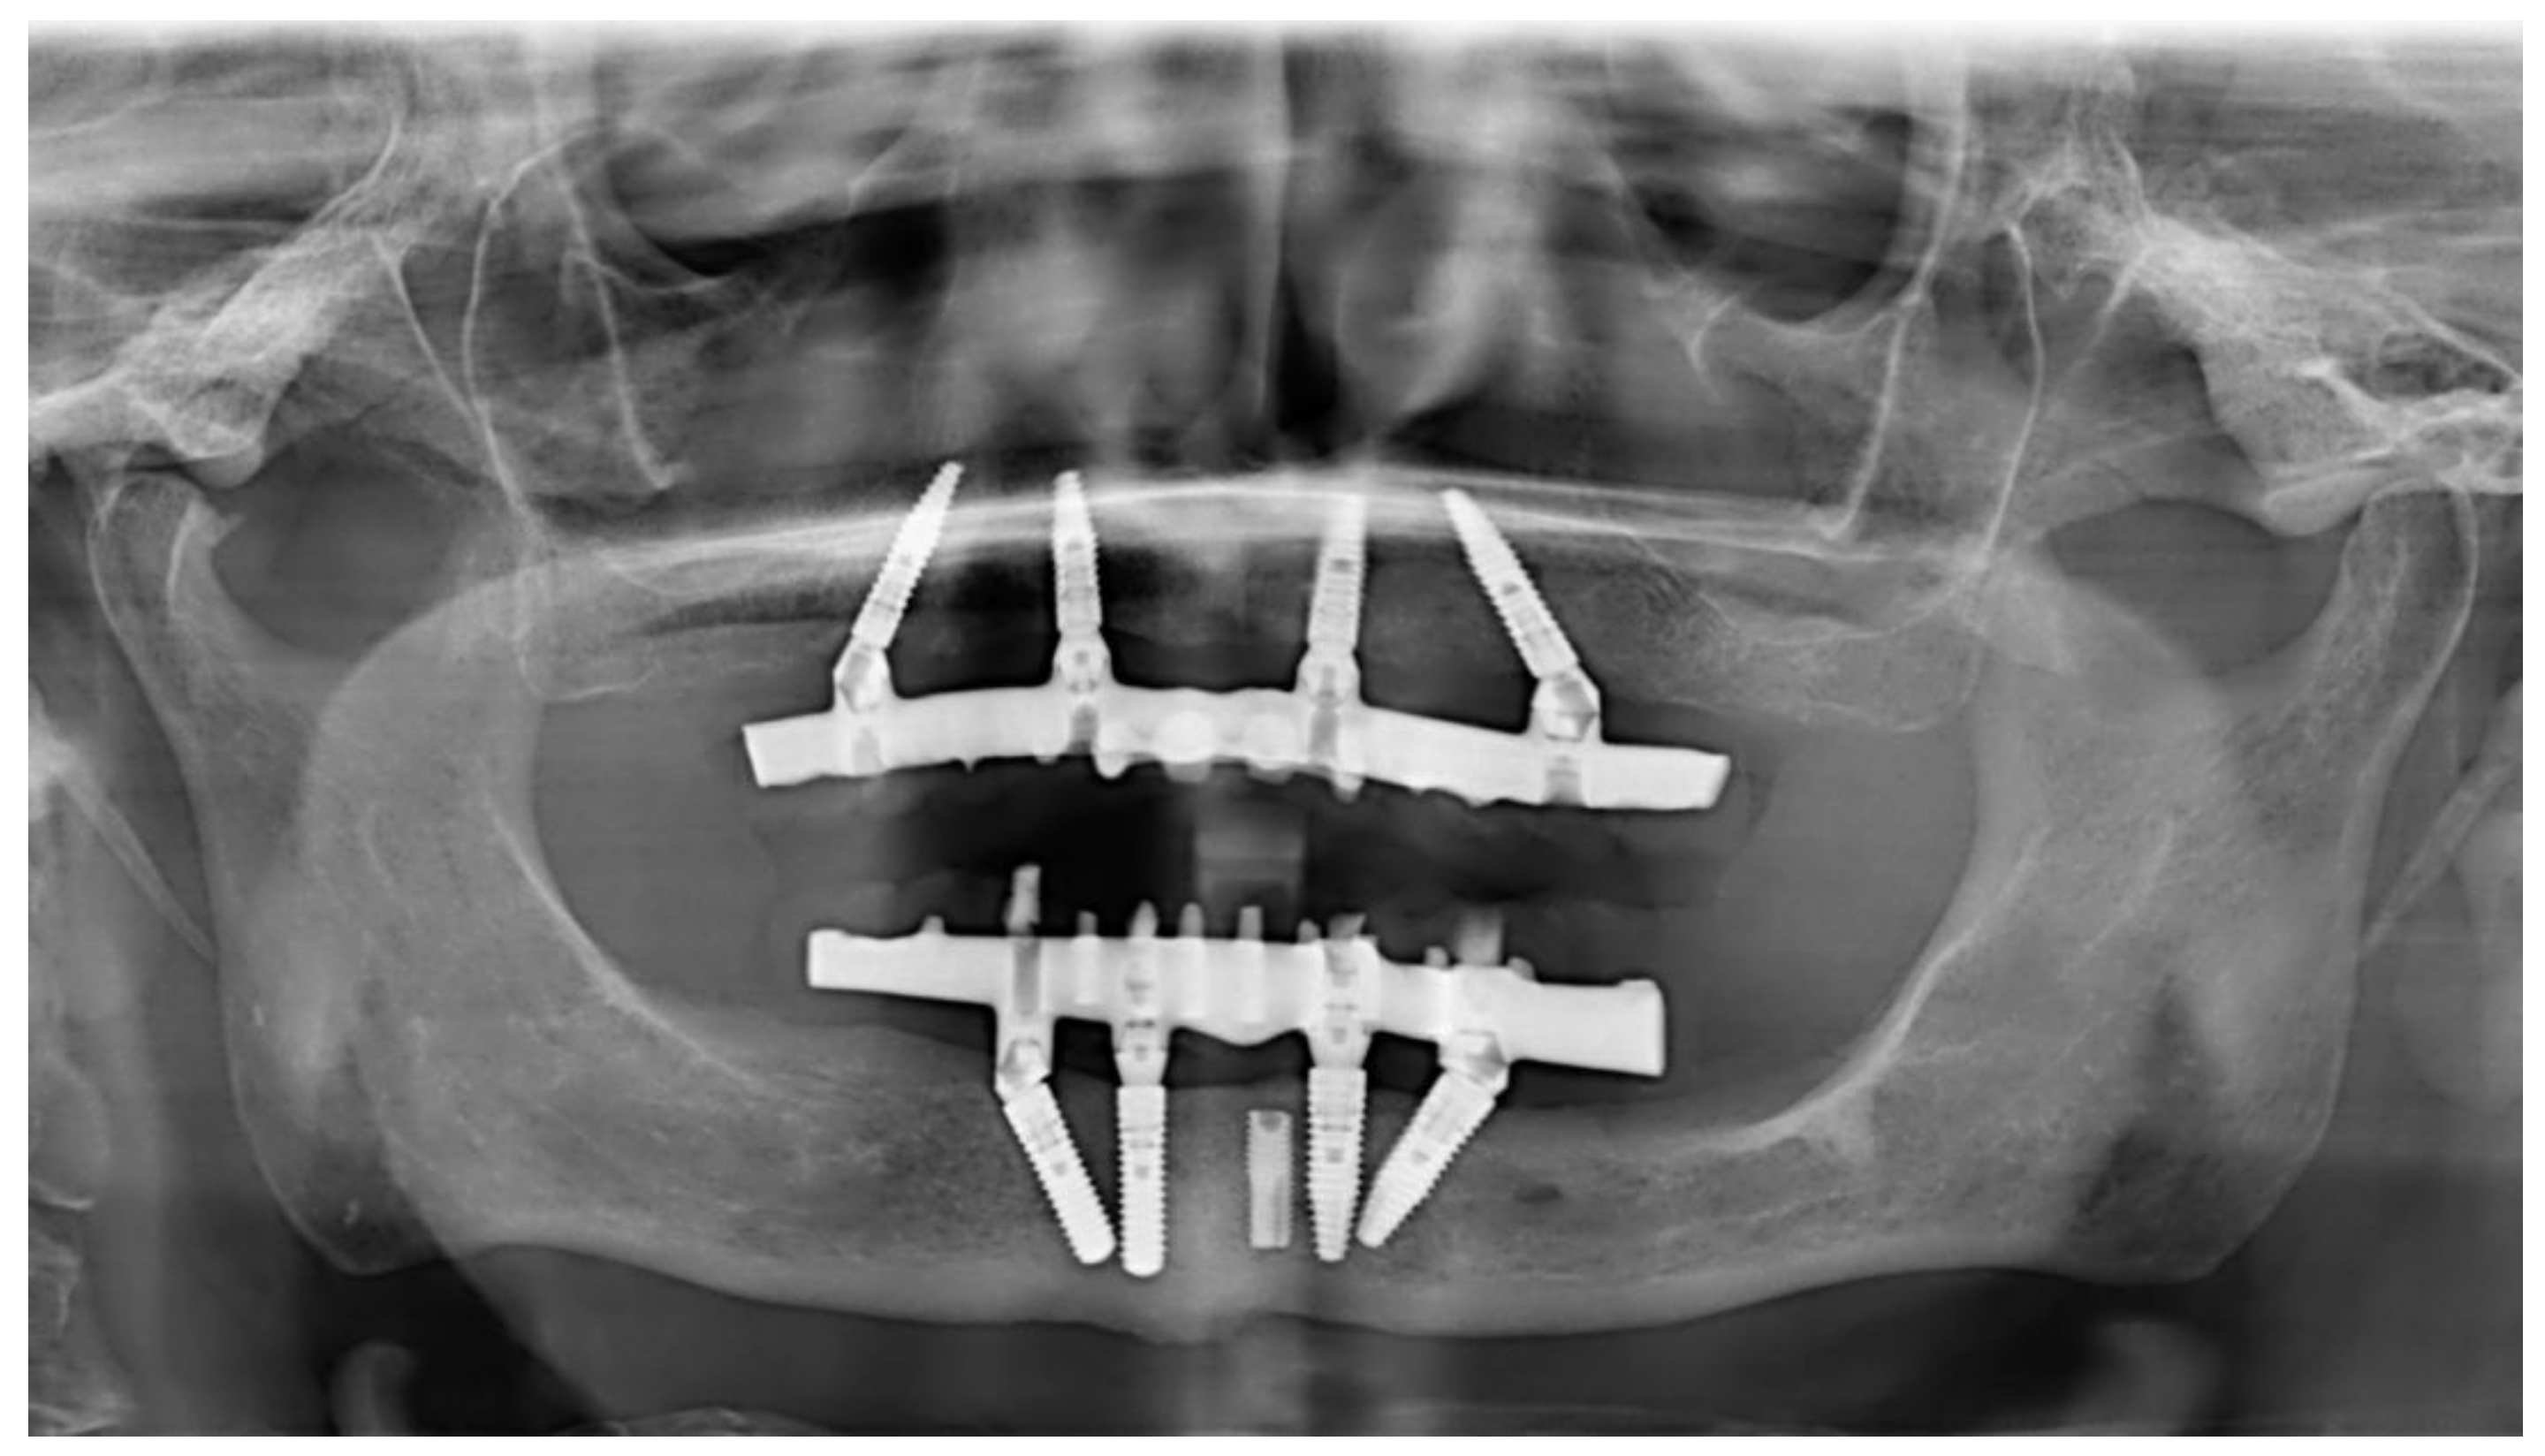

Figure 8.

Panoramic radiograph after 7 years of use in maxillary-implant-supported rehabilitation. In the mandible, the same treatment was performed with standard-diameter implants. One previously placed implant had fractured and was left in the subgingival region. It was not included in the rehabilitation treatment.